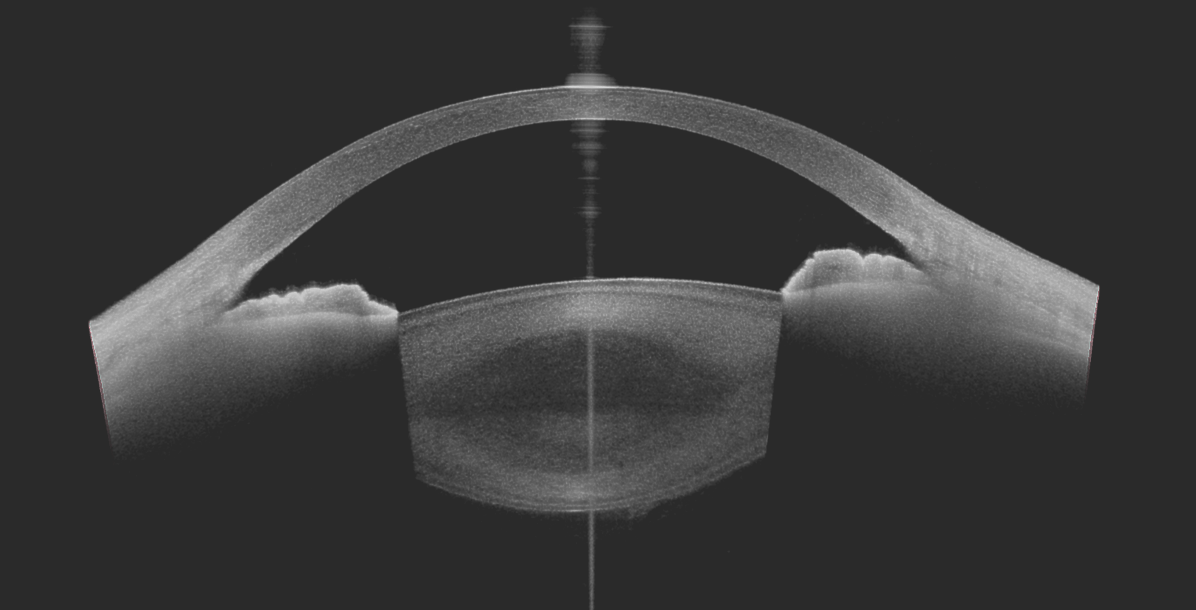

UBM (Echographie Haute Fréquence)

Echographie analysant l'ouverture de l'angle entre l'iris et la cornée et l'aspect de l'iris.

En cas d'angle fermé, le risque de glaucome aigu à angle fermé doit faire réaliser un laser préventif.

OCT SEGMENT ANTERIEUR

Tomographie à cohérence optique s'intéressant à la cornée et aux angle irido-cornéen.

Examen réalisé dans l'étude des anomalies de la cornée et de l'angle irido-cornéen.